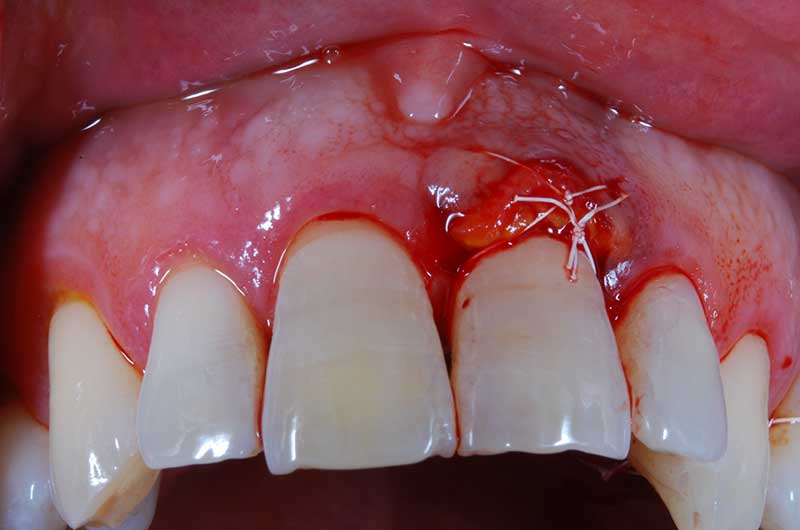

I denti irrecuperabili dell'arcata superiore ed inferiore del paziente di anni 65

sono stati sostituiti da 10 impianti, cioè protesi radicolari endo-ossee che sostengono le protesi fisse superiore ed inferiore.